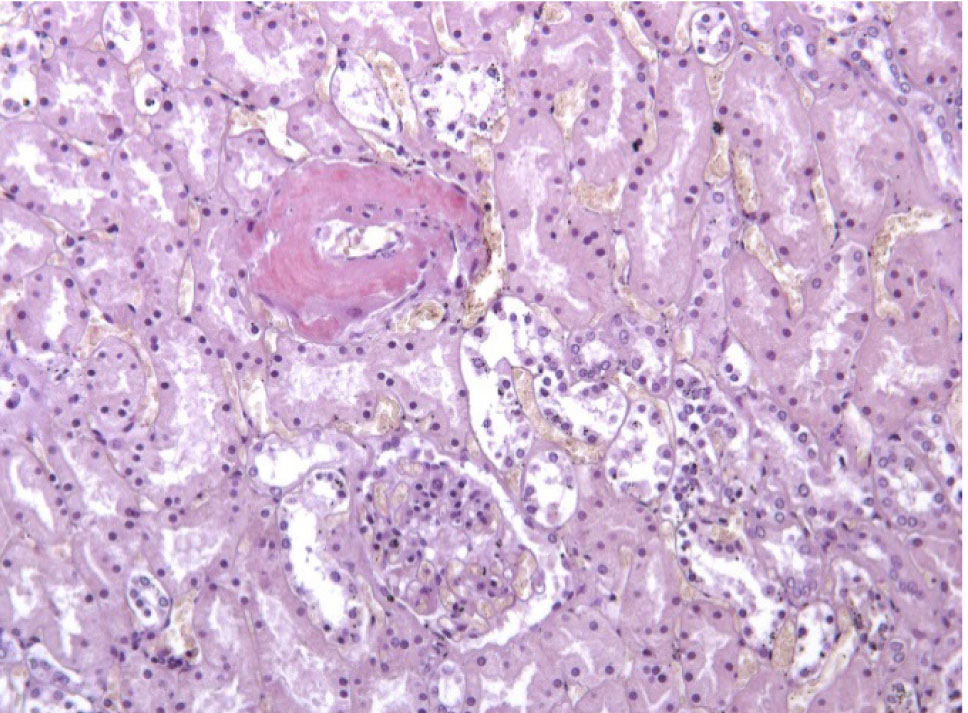

Почки – резкое уменьшение числа клубочков, отдельные полностью замещены однородной массой, дающей положительную реакцию на амилоид (рис. 3). В стенке сосудов также видны отложения амилоида (рис. 4).

Рис. 3. Почечный клубочек замещен амилоидными массами. Окраска конго красный, ×400

Рис. 4. Амилоид в стенке сосуда в почке. Окраска конго красный, ×200